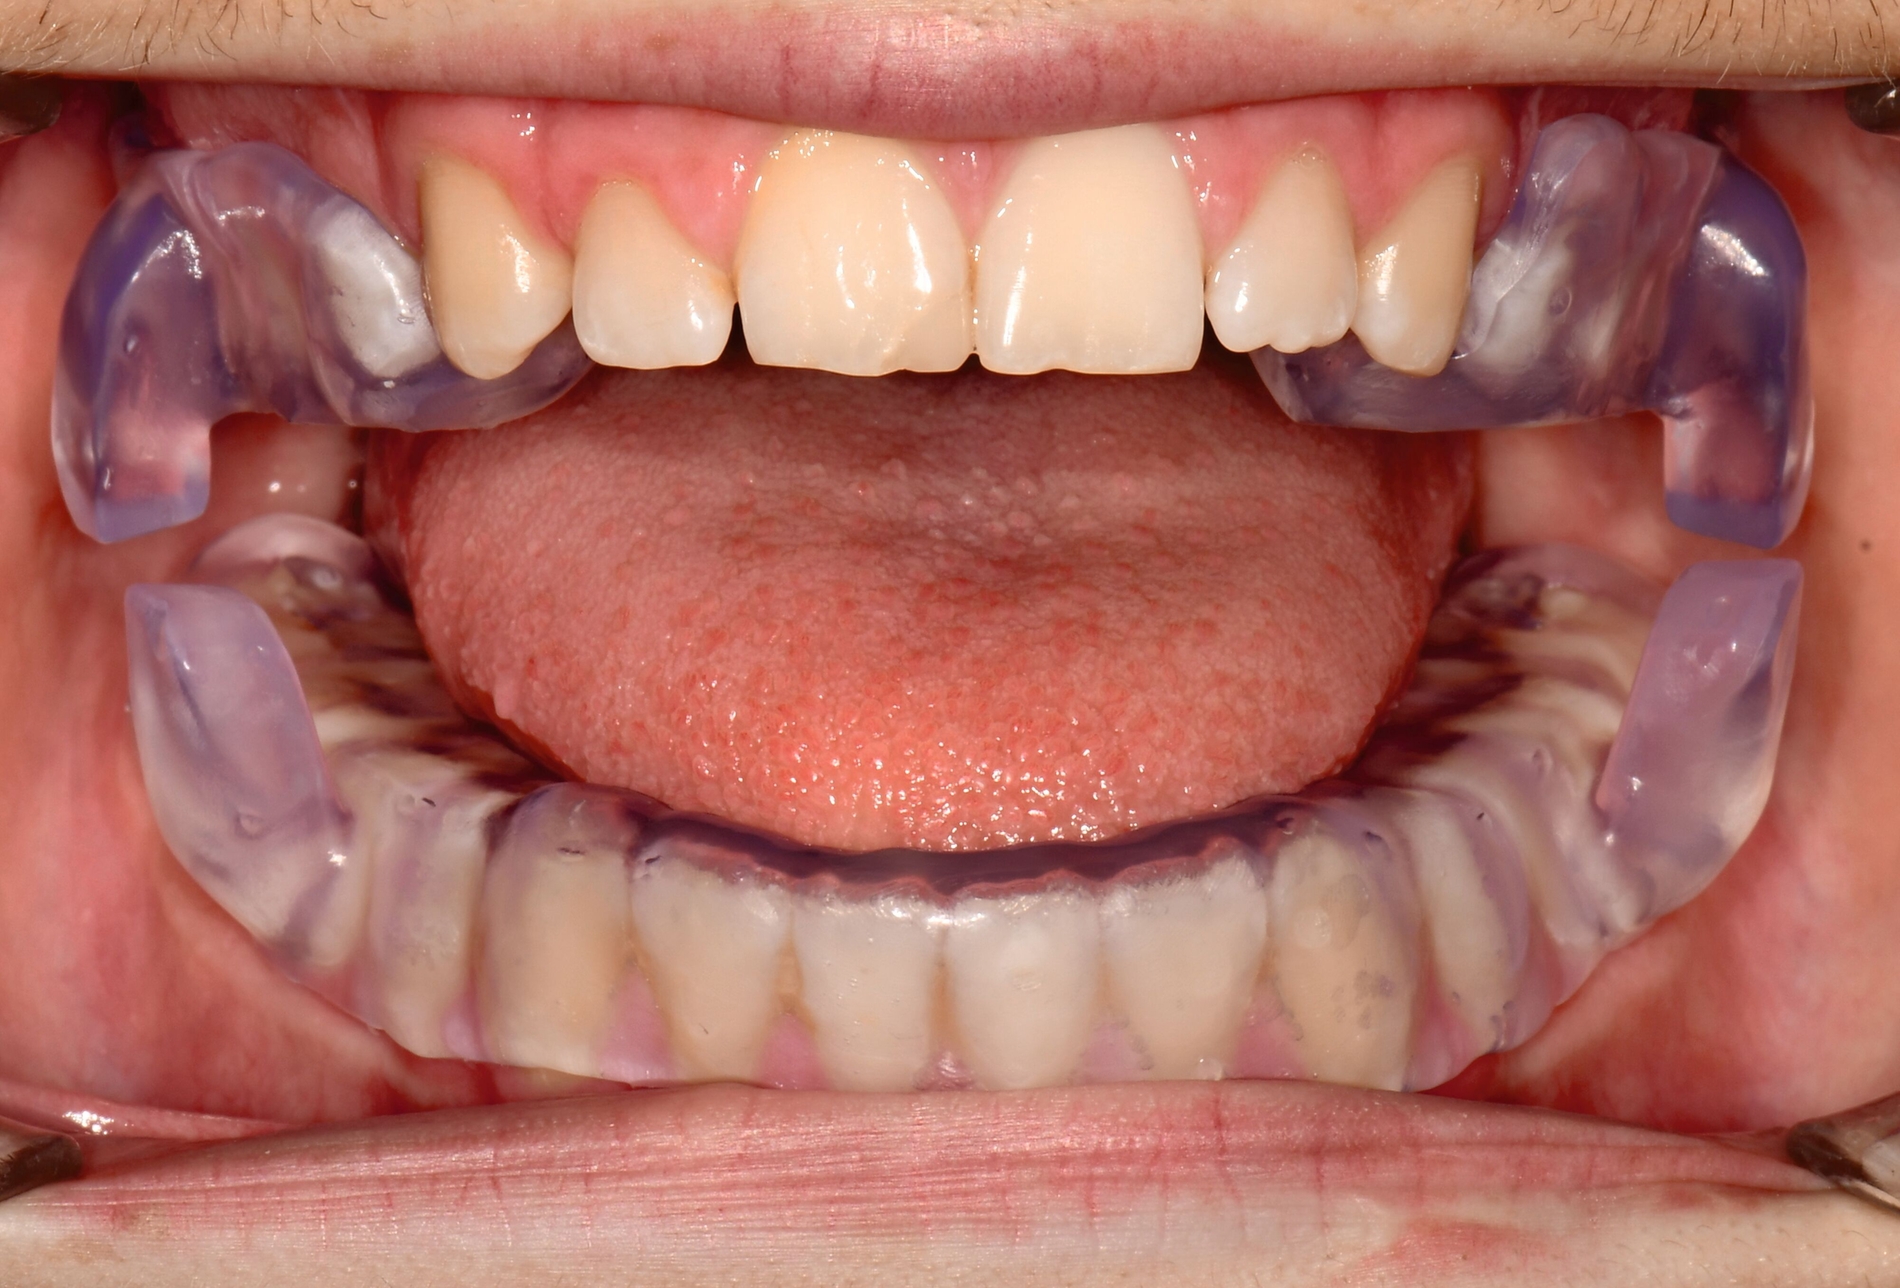

Herausnehmbare Apparaturen

Als hochinnovatives Feld hat sich auch die Herstellung herausnehmbarer Apparaturen im 3-D-Druck entwickelt (Abbildung 4), beschränkt sich jedoch noch auf einzelne Forschungsansätze [Al Mortadi et al., 2012; van der Meer et al., 2016; Graf et al., 2022; Keller et al., 2022]. Intensiv an neuen Konzepten in der Herstellung 3-D-gedruckter herausnehmbarer Apparaturen wird am Universitätsklinikum Heidelberg geforscht. Da herausnehmbare kieferorthopädische Apparaturen im Regelfall bei jungen Patienten eingesetzt werden, kommt dem Vorteil einer unbegrenzten Replikation und einer kostengünstigen und schnelleren Herstellung ein besonderer Stellenwert zu.

Im Unterschied zu konventionellen Apparaturen bestehen die 3-D-gedruckten Apparaturen vollkommen aus Kunststoff. Eine Einarbeitung metallischer Elemente nach dem 3-D-Druck ist möglich [Al Mortadi et al., 2012; Al Mortadi et al., 2024], erfordert jedoch zusätzlichen Zeitaufwand. Zur Herstellung herausnehmbarer Apparaturen eignen sich konventionelle praxisinterne 3-D-Stereolithografie-Drucker, die in vielen Fällen bereits im regulären Praxisalltag zum Modelldruck verwendet werden. Die verwendeten Kunststoffe sollten dabei eine Klasse-IIa-Zertifizierung aufweisen, so dass ein sicherer langfristiger intraoraler Einsatz der Apparatur gewährleistet ist. Weiter muss die Apparatur nach dem 3-D-Druck gemäß den Herstellerangaben nachprozessiert werden. Im Regelfall beinhaltet dieser Prozess ein Waschen in Isopropylalkohol (IPA) sowie eine Nachhärtung im Lichthärtegerät. Eigens durchgeführte Studien sowie die bisherige klinische Erfahrung bestätigen eine hohe mechanische Stabilität, eine hohe Passgenauigkeit sowie eine breite Akzeptanz der Patienten [Roser et al., 2021; Roser et al., 2023; Segnini et al., 2023]. Des Weiteren wecken die 3-D-gedruckten Apparaturen bei den meist jungen Patienten großes Interesse, was wiederum die Trage-Compliance unterstützt. Durch weitere Entwicklungen im 3-D-Druckbereich wird zukünftig auch ein Farbdruck möglich werden.